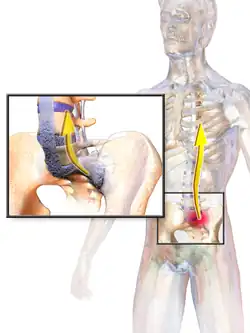

AS can occur in any part of the spine or the entire spine, often with pain localized to either buttock or the back of the thigh from the sacroiliac joint. Arthritis in the hips and shoulders may also occur. When the condition presents before the age of 18, AS is more likely to cause pain and swelling of large lower limb joints, such as the knees.[13] In prepubescent cases, pain and swelling may also manifest in the ankles and feet where heel pain and enthesopathy commonly develop.[13] Less common occurrences include ectasia of the sacral nerve root sheaths.[14]